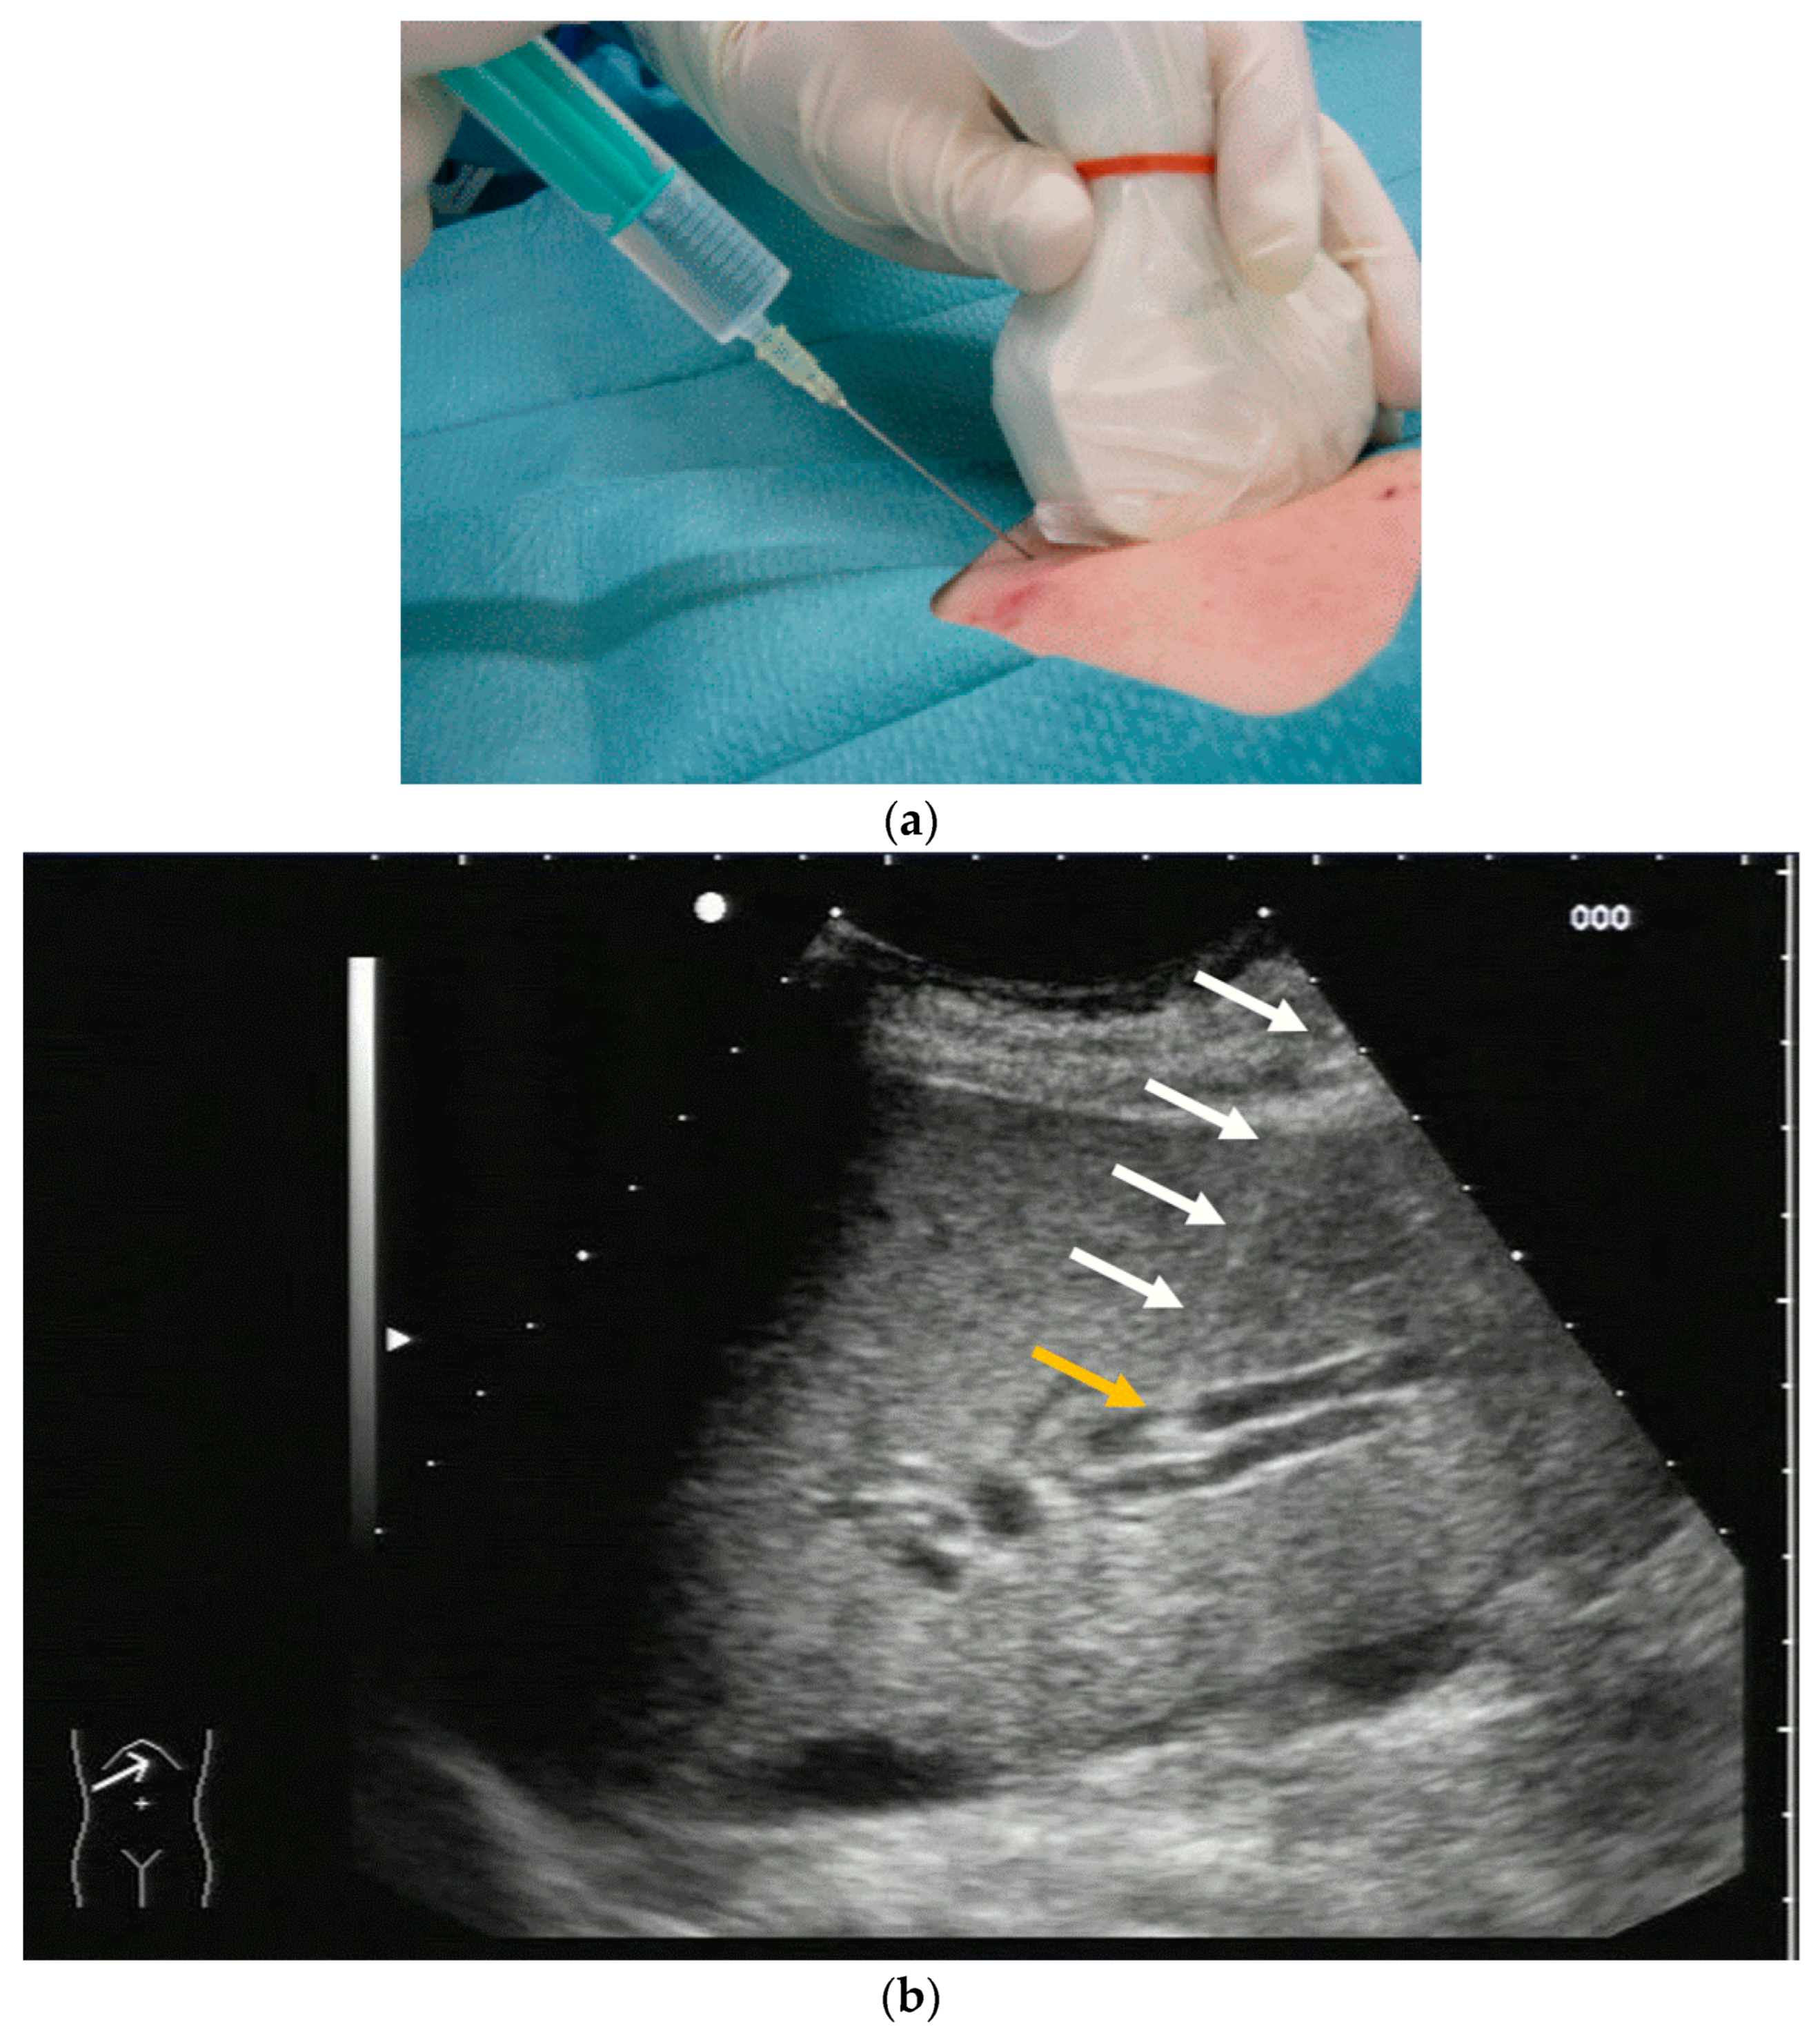

Most authors recommend a transhepatic approach in order to prevent biliary leakage to the abdominal cavity during drainage or after removal of drainage [43,55,56,76,77] (Figure 9).

Figure 9.

(a) Transhepatic puncture of an inflamed gall bladder in the in-plane technique. The Chiba needle is depicted well; (b) A few days later, laparoscopic cholecystectomy was performed. The drainage ran through Segment V of the liver. It was removed without provoking biliary leakage from the liver parenchyma.

The consideration is that a perforation in the hepatic surface of the gallbladder will be covered by the liver tissue after the removal of the drain. However, retrospective analyses comparing the transhepatic route with the transperitoneal (i.e., nontranshepatic) access (Figure 10) report no differences in the complication rates [58,78,79].

Again, the “in plane” approach is recommended to depict the needle in real time and continuously on its way. This is mandatory because iatrogenic perforation of the posterior gallbladder wall must be avoided. Both the drainage techniques, Seldinger (Figure 11a–c) and trocar (direct puncture, cf. Figure 10), may be used, depending on the physician’s preferences [43,58].